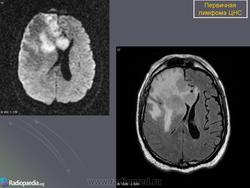

Первичные лимфомы ЦНС. Вс, 22/05/2011 - 21:45 #1 Катенёв Валенти... Не на сайте Был на сайте: 7 лет 5 месяцев назад Зарегистрирован: 22.03.2008 - 22:15 Публикации: 54876 Продолжение.Приложения:

Продолжение.